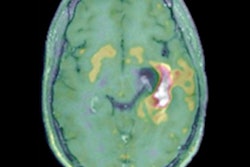

A new two-center French study has shown the high accuracy of F-18 fluorodopa PET for differentiating recurrent malignant gliomas from treatment-related changes. It has also underlined the importance of the dynamic slope as a potential diagnostic and prognostic biomarker in isocitrate dehydrogenase gliomas. Find out more in today's top article.